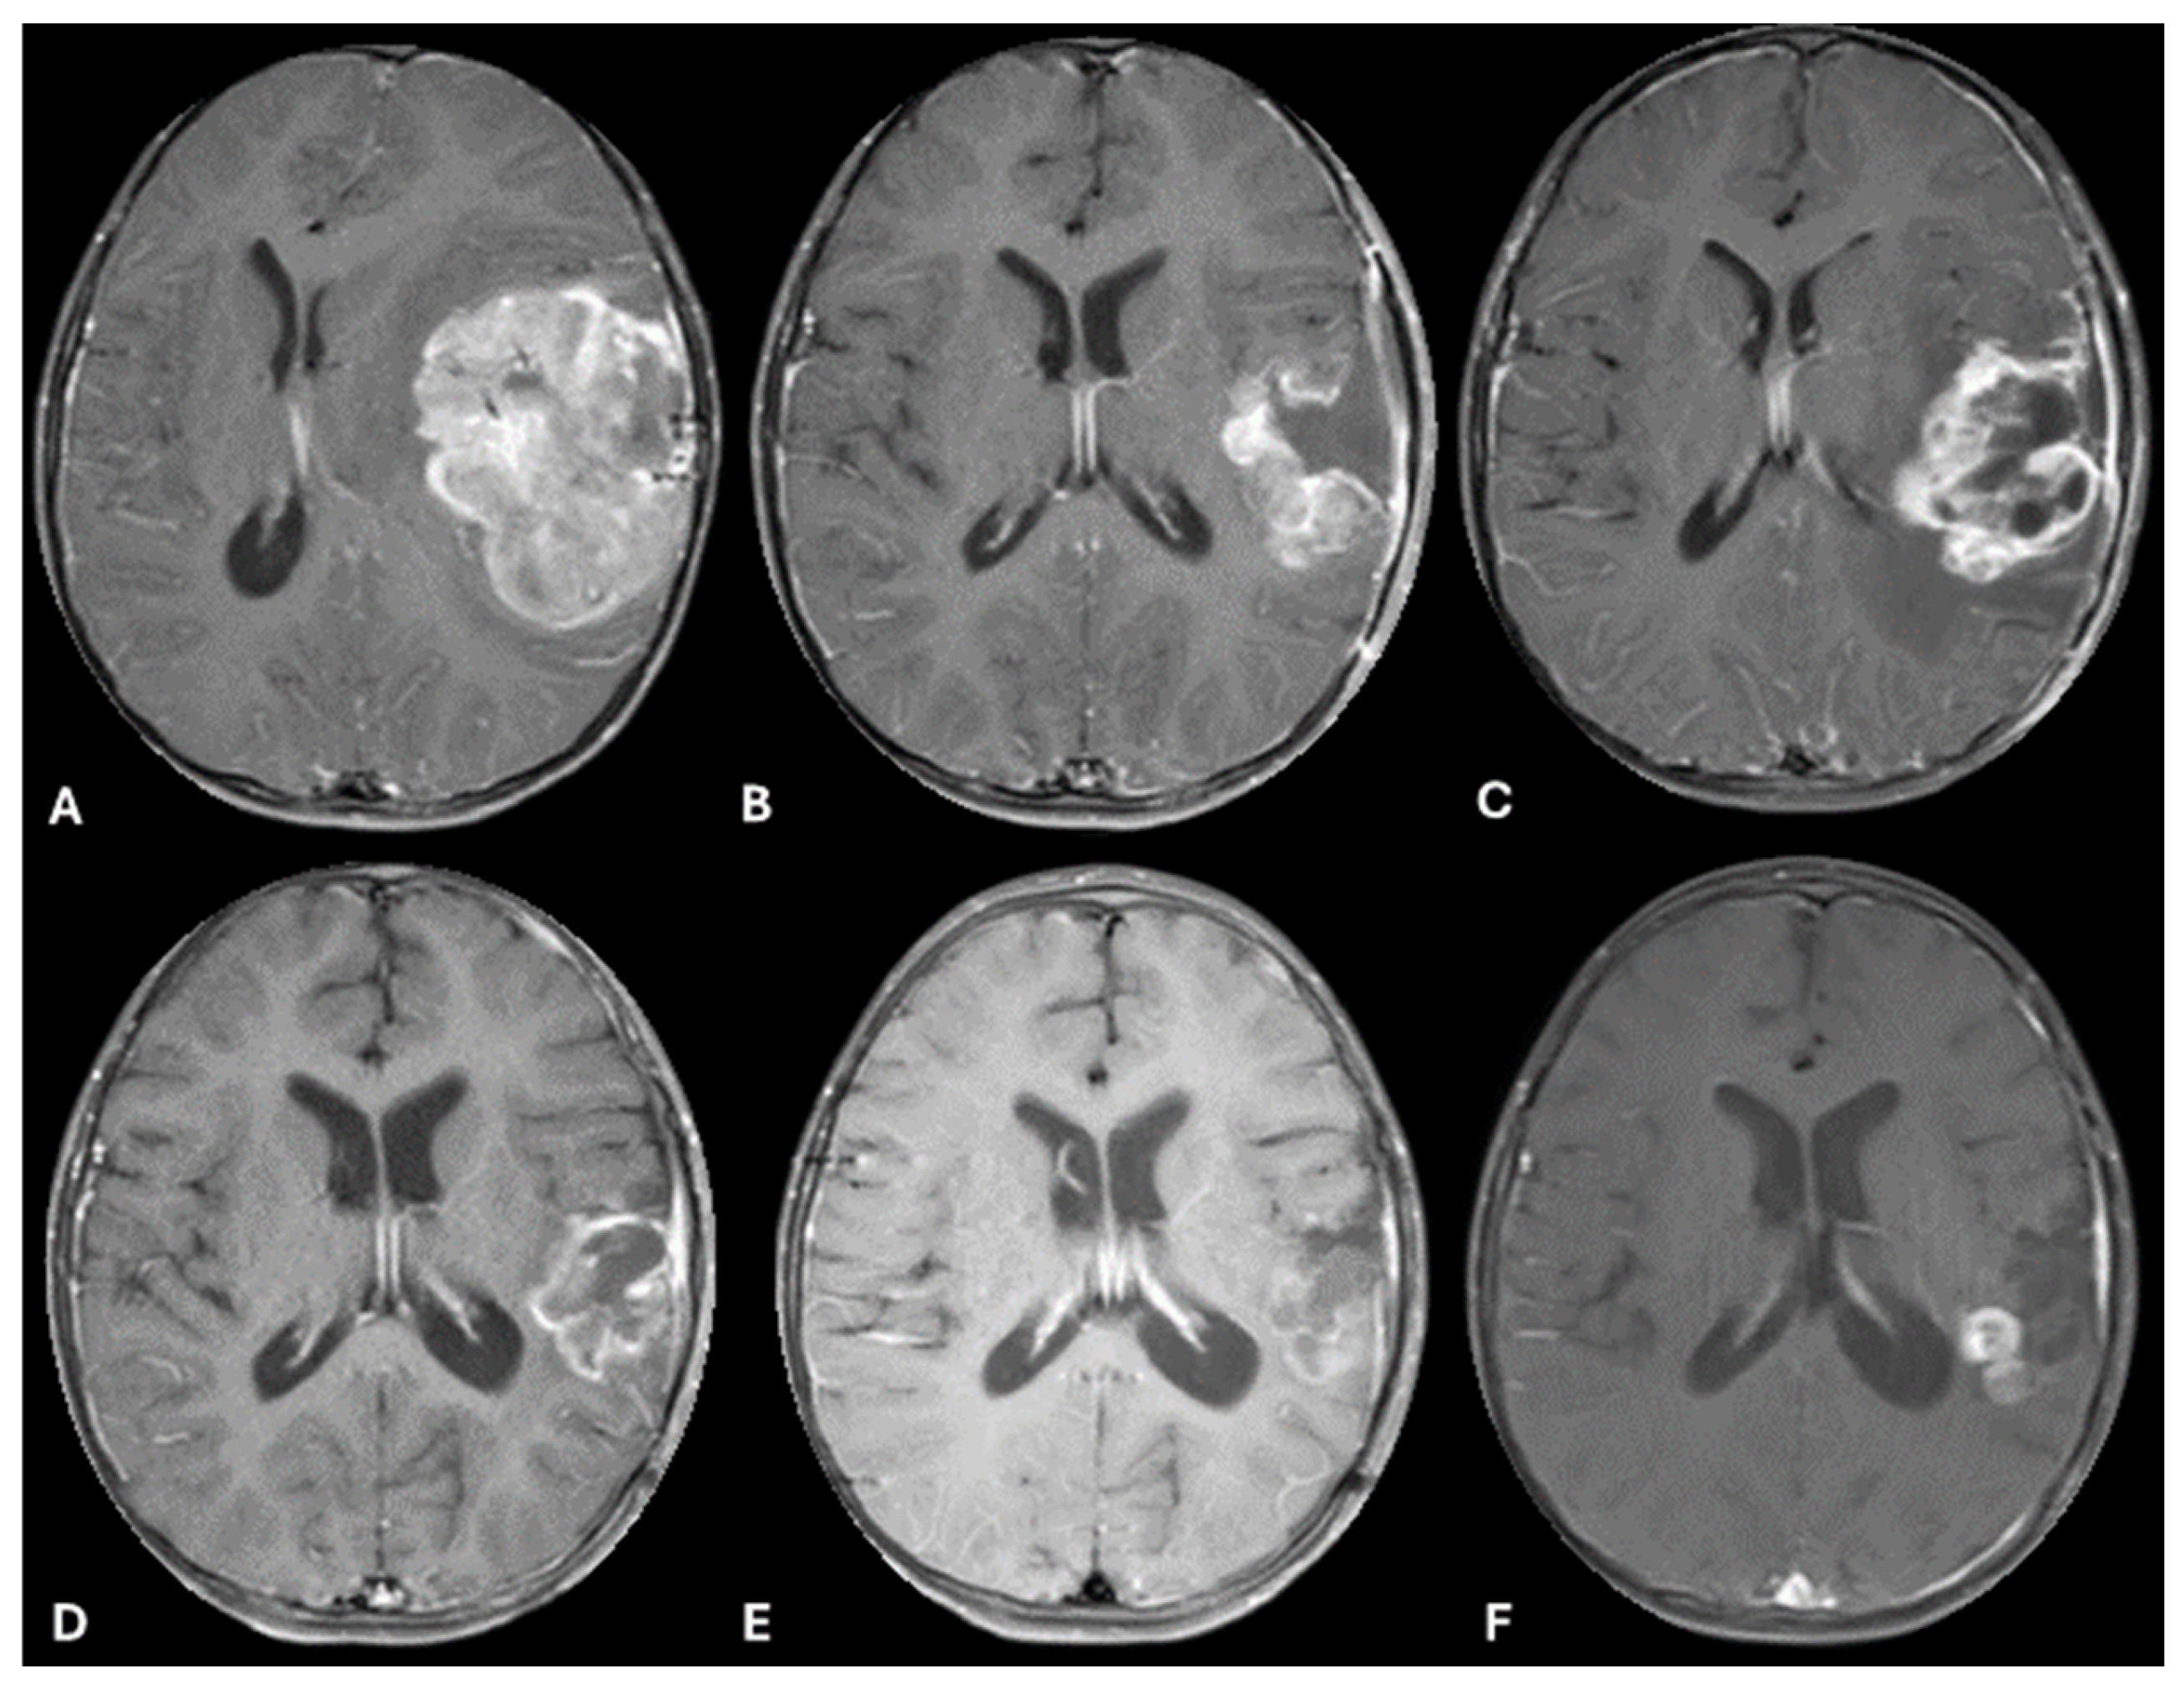

| Patient 1 | Diagnostic | -Brisk mitotic activity -Gliosis in myxoid background -Vimentin positive -olig2 positive -S-100 positive | -CLIP2-MET fusion -CHEK2 frameshift alteration -CDKN2A, CDKN2B, MTAP loss | Infant-type Hemispheric Glioma | Infant-type Hemispheric Glioma, WHO-CNS Grade 4 | Systemic chemotherapy: Cyclophosphamide, Vincristine, Cisplatinum and Etoposide (2 cycles) Targeted agent: Cabozantinib |

| Patient 2 | Diagnostic | -Brisk mitotic activity -INI1 retained -P53 diffusely expressed -olig2 positive | -MBOAT2-ALK fusion -TP53 loss -MYCN copy gain | Diffuse Pediatric-type High-Grade Glioma, MYCN subtype | Diffuse Pediatric-type High-Grade Glioma, H3-wild-type and IDH-wild-type, CNS WHO Grade 4 | Radiotherapy with concurrent Temozolomide Targeted agent: Lorlatinib |

| Relapse | Similar to diagnostic sample, with olig2 loss | -MET copy gain -MBOAT2-ALK fusion -TP53 loss -MYCN copy gain | Diffuse Pediatric-type High-Grade Glioma, MYCN subtype | Diffuse Pediatric-type High-Grade Glioma, H3-wild-type and IDH-wild-type, CNS WHO Grade 4 | Target agents: Lorlatinib and Cabozantinib |